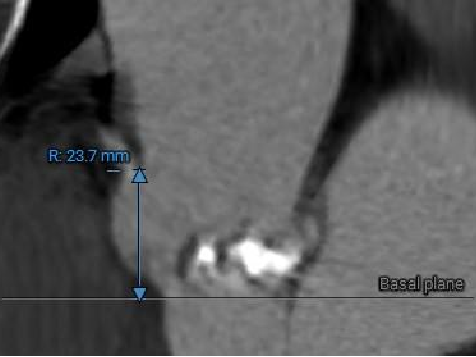

冠脉风险评估

LCA Height

RCA Height